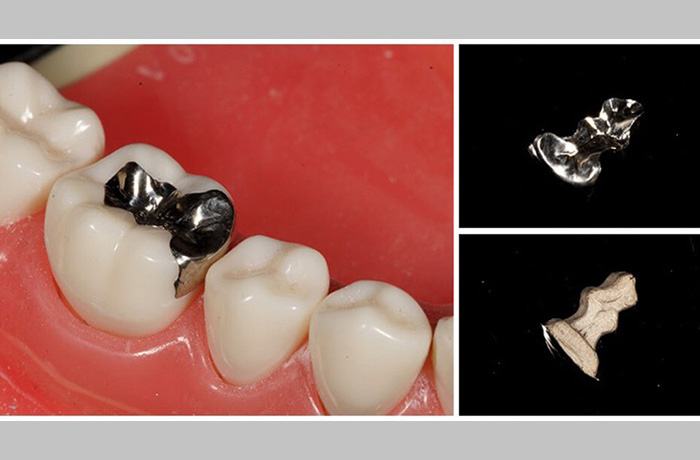

8 つめ物・かぶせ物がよく外れる

つめ物の銀歯やかぶせ物のクラウンが外れる時は、虫歯かセメントの寿命になります。歯ぎしり・食いしばりが強い方は、このセメントの寿命が早まってしまうがためによく外れるという現象が起きます。

通常の食事などでセメントが破壊されて外れることは、まずないと言われていますので、やはり良くつめ物・かぶせ物が外れる場合は、歯ぎしり・食いしばりを疑うようにしてください。